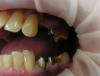

Art 7 Опубликовано 4 февраля, 2013 Поделиться Опубликовано 4 февраля, 2013 точность 1 Ссылка на комментарий

Rtov Опубликовано 4 февраля, 2013 Поделиться Опубликовано 4 февраля, 2013 точностьхорошо! только, слепочный (база) от борта далековато как-то,как там со стабильностью?а вот так делают зачастую в поликлиниках( Ссылка на комментарий

Rtov Опубликовано 4 февраля, 2013 Поделиться Опубликовано 4 февраля, 2013 со стабильностью чего?не надо вешать клеймо на поликлиники,я там работая делал с высокой точностью (с большими усилиями конечно и не всегда) но делалстабильность посредственная,обратите внимание на толщину цем. слоя! Ссылка на комментарий